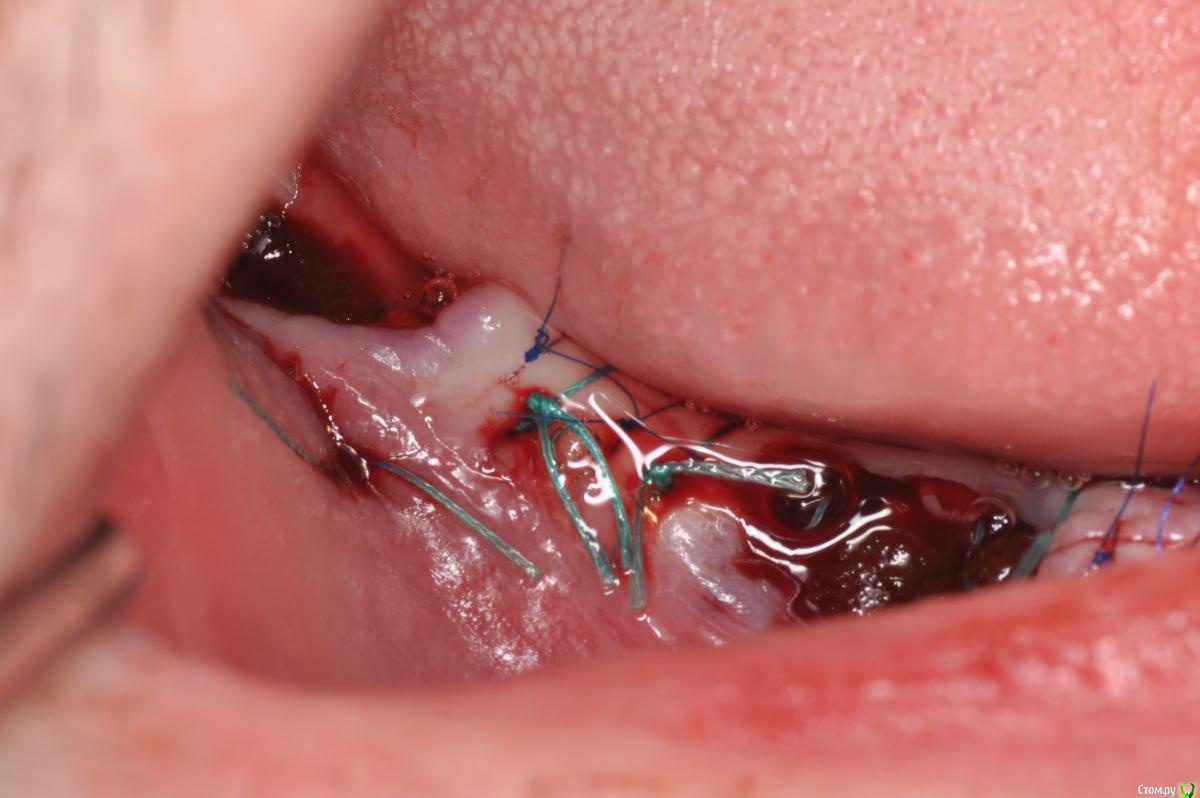

kriokov Опубликовано 23 ноября, 2015 Поделиться Опубликовано 23 ноября, 2015 а через пол года я этим Фторэксом ботинок себе заштопал на работе!) добраться до дома должно хватитьфторэкс в сравнении с унифлекс сразу в день вмешательствачерез 2 сутокчерез 8 суток фторэкс надулся и весь в дерьмецеснял фторэкс, дырки после него на раневой здоровыеснял все, слизистая как после дратвы где был фторэкс Ссылка на комментарий